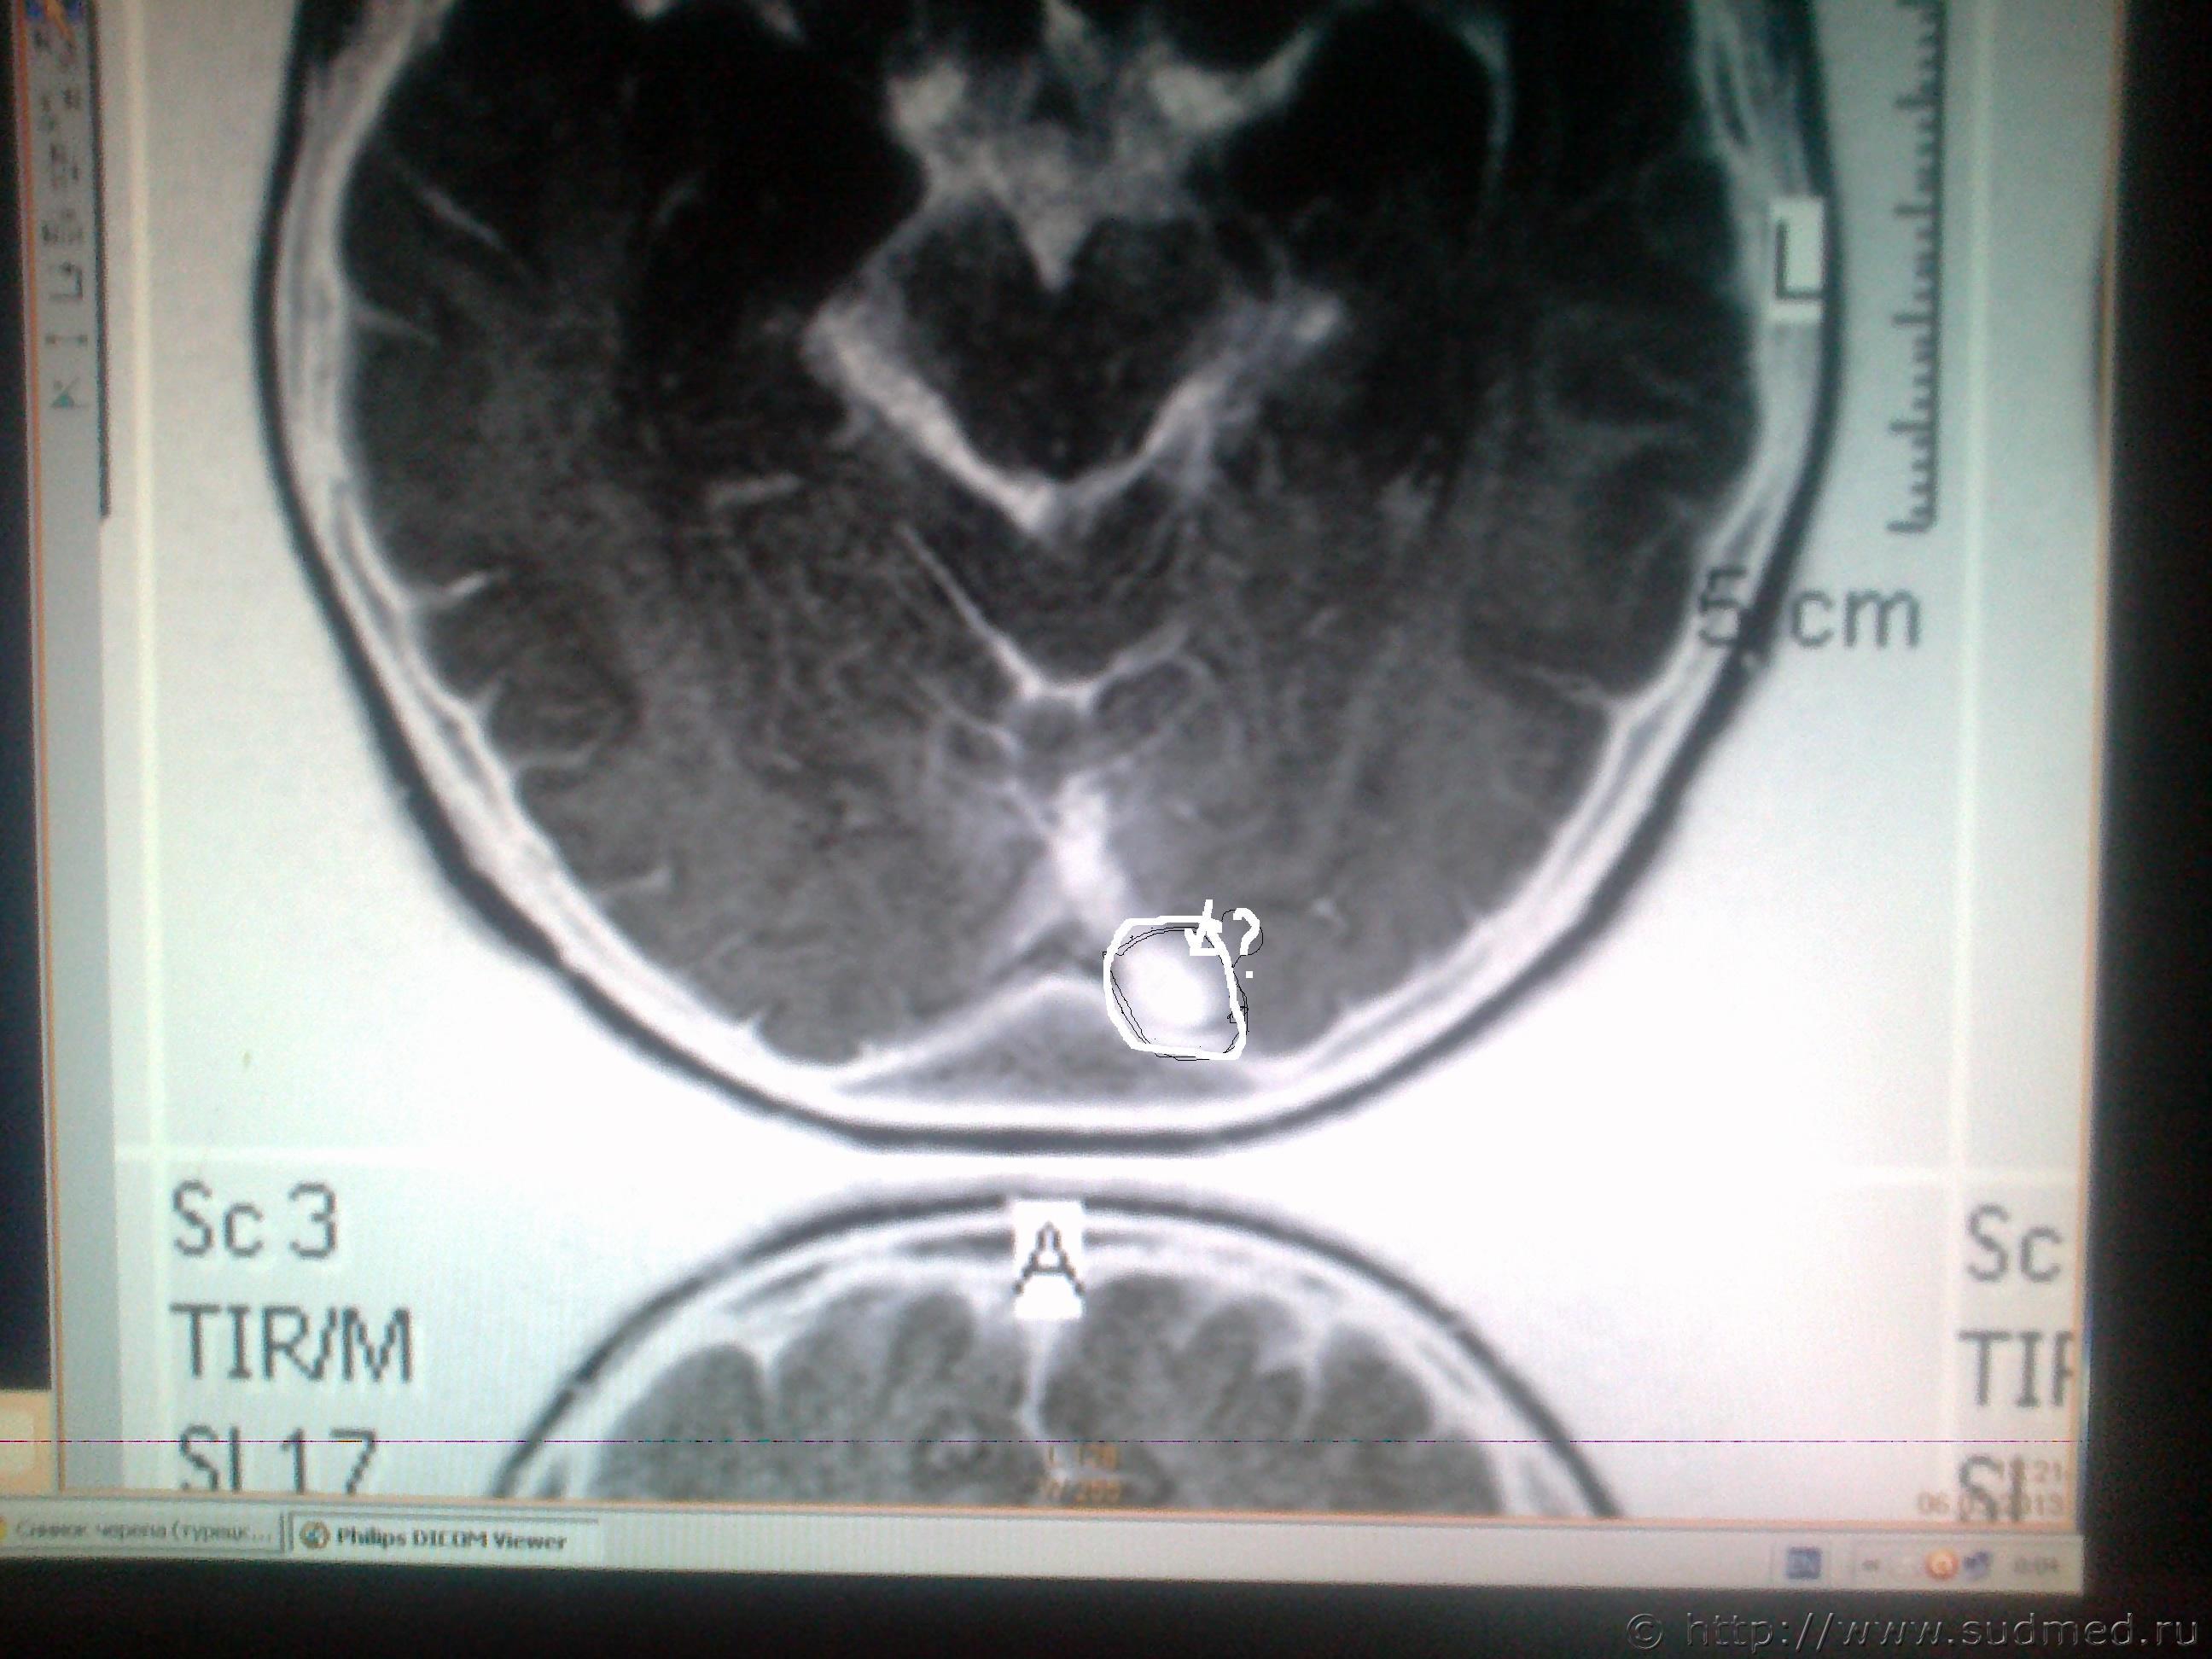

ув. специалисты! Мне оч. хочется узнать ваше мнение, что показано на мрт снимках в мозгу и на костной ткани, интересующие места обведены. Есть ли трещины на костях черепа или это шов и что значит чёрное- белое пятно на снимке мозга?

Светичок! Надо показать сами эти снимки специалисту по МРТ (на пленке и/или на электронном носителе. На эл.носителе даже лучше, т.к. на пленке могут быть распечатаны, к примеру, 30 сканов, а, фактически, их 150 было выполнено и все они могут быть представлены Вам на диске или на флешке). Присланное Вами хуже по качеству, чем снимки, которые есть фактически и, на этом форуме, насколько мне известно, нет врачей имеющих сертификат по специальности"Рентгенология" и дополнительную специальную подготовку по ядерно-магнито-резонансной томографии. Поищите какой-нибудь форум рентгенологов, вероятно, там смогут дать более компетентные комментарии. Насколько я разбираюсь в МРТ (немножко): на снимках №1, 2 и 3 - вероятнее всего, ликворная киста. Возможно, это вариант развития, возможно, след от давно регрессировавшей (прошедшей, рассосавшейся) гематомы. В любом случае, даже если это изменение имеет посттравматическое происхождение, то травма была давно (месяцы или годы назад), на что указывает отсутствие признаков внутричерепной гематомы, перифокального отека вещества головного мозга. Только по этим снимкам ни один специалист не сможет серьезно и аргументированно доказать, что это: 1.именно последствие травмы и ни что другое, 2.точно установить дату этой предполагаемой травмы. (Просьба не путать специалиста с шарлатаном, который, "все что угодно за ваши деньги" - в суде такое "заключение" окажется несостоятельным). На снимках №4 и 5 - шов между затылочной и теменными костями, №6 - каналы диплоэтических вен (вены, проходящие сквозь кости черепа. Они извитые, а перелом, в такой проекции выглядит как прямая линия, перпендикулярно и косо-перпендикулярно пересекающая кость свода черепа). МРТ - неоптимальный метод для оценки состояния костей свода черепа (МРТ - великолепный метод для оценки состояния мягких тканей). Гораздо лучше - обычная рентгенография костей свода черепа. Желательно,сделанная на современном цифровом рентгеновском аппарате. Желательно - полипозиционная (т.е. не только стандартные снимки в прямой и одной из боковых проекций, а, в данном случае - прямая проекция,правая и левая боковые проекции, контактная рентгенограмма затылочной кости и, возможно, снимок с выведением места предполагаемого перелома в краеобразующую зону. Тогда на 100% будет понятно,что это такое. Вероятно, на 100% будет понятно уже на стадии рентгенограмм в прямой и боковых проекциях. Грамотный рентгенолог знает все это лучше, чем я тут написал). Можно, конечно, сделать мультиспиральную компьютерную томографию /МСКТ/ в костном режиме с 3-D реформацией изображения,однако, лучевая нагрузка будет больше, а информативность - сопоставимая. Если в итоге найдется что-то похожее на посттраматические изменения, то нужно будет провести исследование всех рентгенограмм, которые выполнялись непосредственно после конкретной травмы, если когда-то до неё делались рентгенограммы, МРТ, КТ головы - их тоже. Это уже задача судебно-медицинской экспертизы. + будут учитываться данные медицинских карт и прочие документы о лечении после этой травмы, о состоянии здоровья до неё и т.п., т.к. перелом кости/костей свода черепа, внутричерепная гематома протекают с весьма выраженной клинической симптоматикой (от чего-то "легкого" и похожего на "сотрясение головного мозга" до тяжелых невропатологических проблем).

Есть заключение только на тему сотрясения общее и на листе где заключение отображены 6 снимков где как раз затылочную часть совсем не видно. Заключение пишу: Объёмных, очаговых или структурных патологических изменений головного мозга и сосудов его артериального круга не выявлено. про кости черепа в направление на мрт не указывалось от сюда и уклон на мозг. снимки на которых написано заключение прилагаю в том виде как они есть на листе бумаги. Те что предоставила ранее, с диска, просто сфотографировала на телефон по ним нет заключения и костей тема не затрагивалась в направление на мрт.

Сотрясение головного мозга по данным МРТ ни один врач (в здравом уме) не установит, т.к. не существует МРТ-симптомов, позволяющих отличить головной мозг абсолютно здорового человека от головного мозга больного с сотрясением головного мозга. Заключение по МРТ краткое. О состоянии костей свода черепа судить по МРТ сложно, так что рентгенолог, в общем-то правильно, что не стал писать про них - каждый метод исследования имеет свои пределы достоверности и информативности. Акцентируйте специалисту интерес именно к местам, обведенным Вами в кружочки.

Приняла решение сходить к ренгенологу и попросить объяснить что же это такое. На сайте по мрт ответ получила под знаком вопроса - ГЕМАТОМА? и пока тишина. Вопрос задала - ЧТО ЭТО МОЖЕТ БЫТЬ?